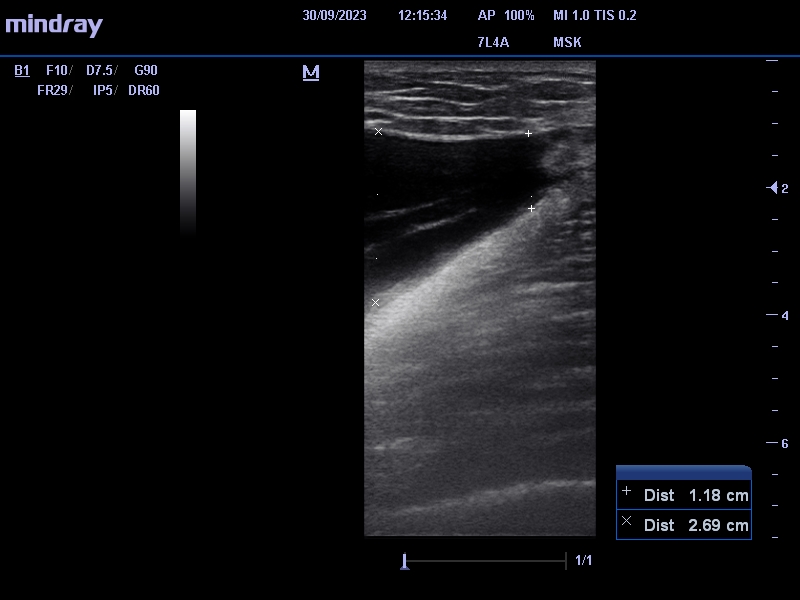

Se identifica entre el tejido celular subcutáneo y la fascia muscular, colección anecogénica, avascular de 2,8 x 17 cm (antero-posterior x craneocaudal) que nos sugiere lesión de Morel-Lavallée.

Se le cita a los 7 días para control ecográfico, donde le extraen 80 cc de contenido y se le pone de nuevo vendaje compresivo. Nueva revisión a la semana encontrándose asintomático y sin recidiva.